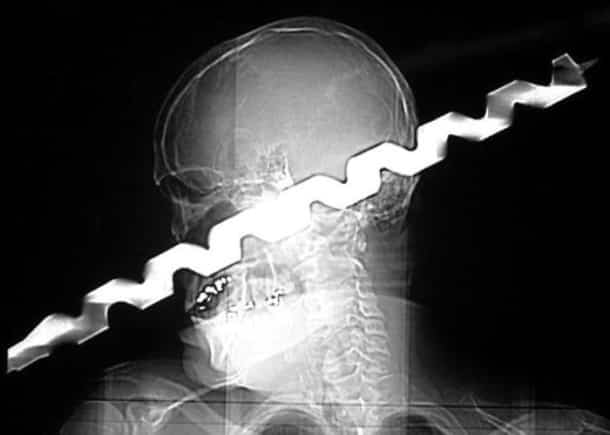

Accident, incident de pistolet à clous ou introductions douteuses de choses douteuses dans des parties douteuses de leur corps…voilà un petit aperçu de ce que voient les médecins au quotidien…

Certaines radiographies sont impressionnantes mais relèvent d’accidents…d’autres en revanche…